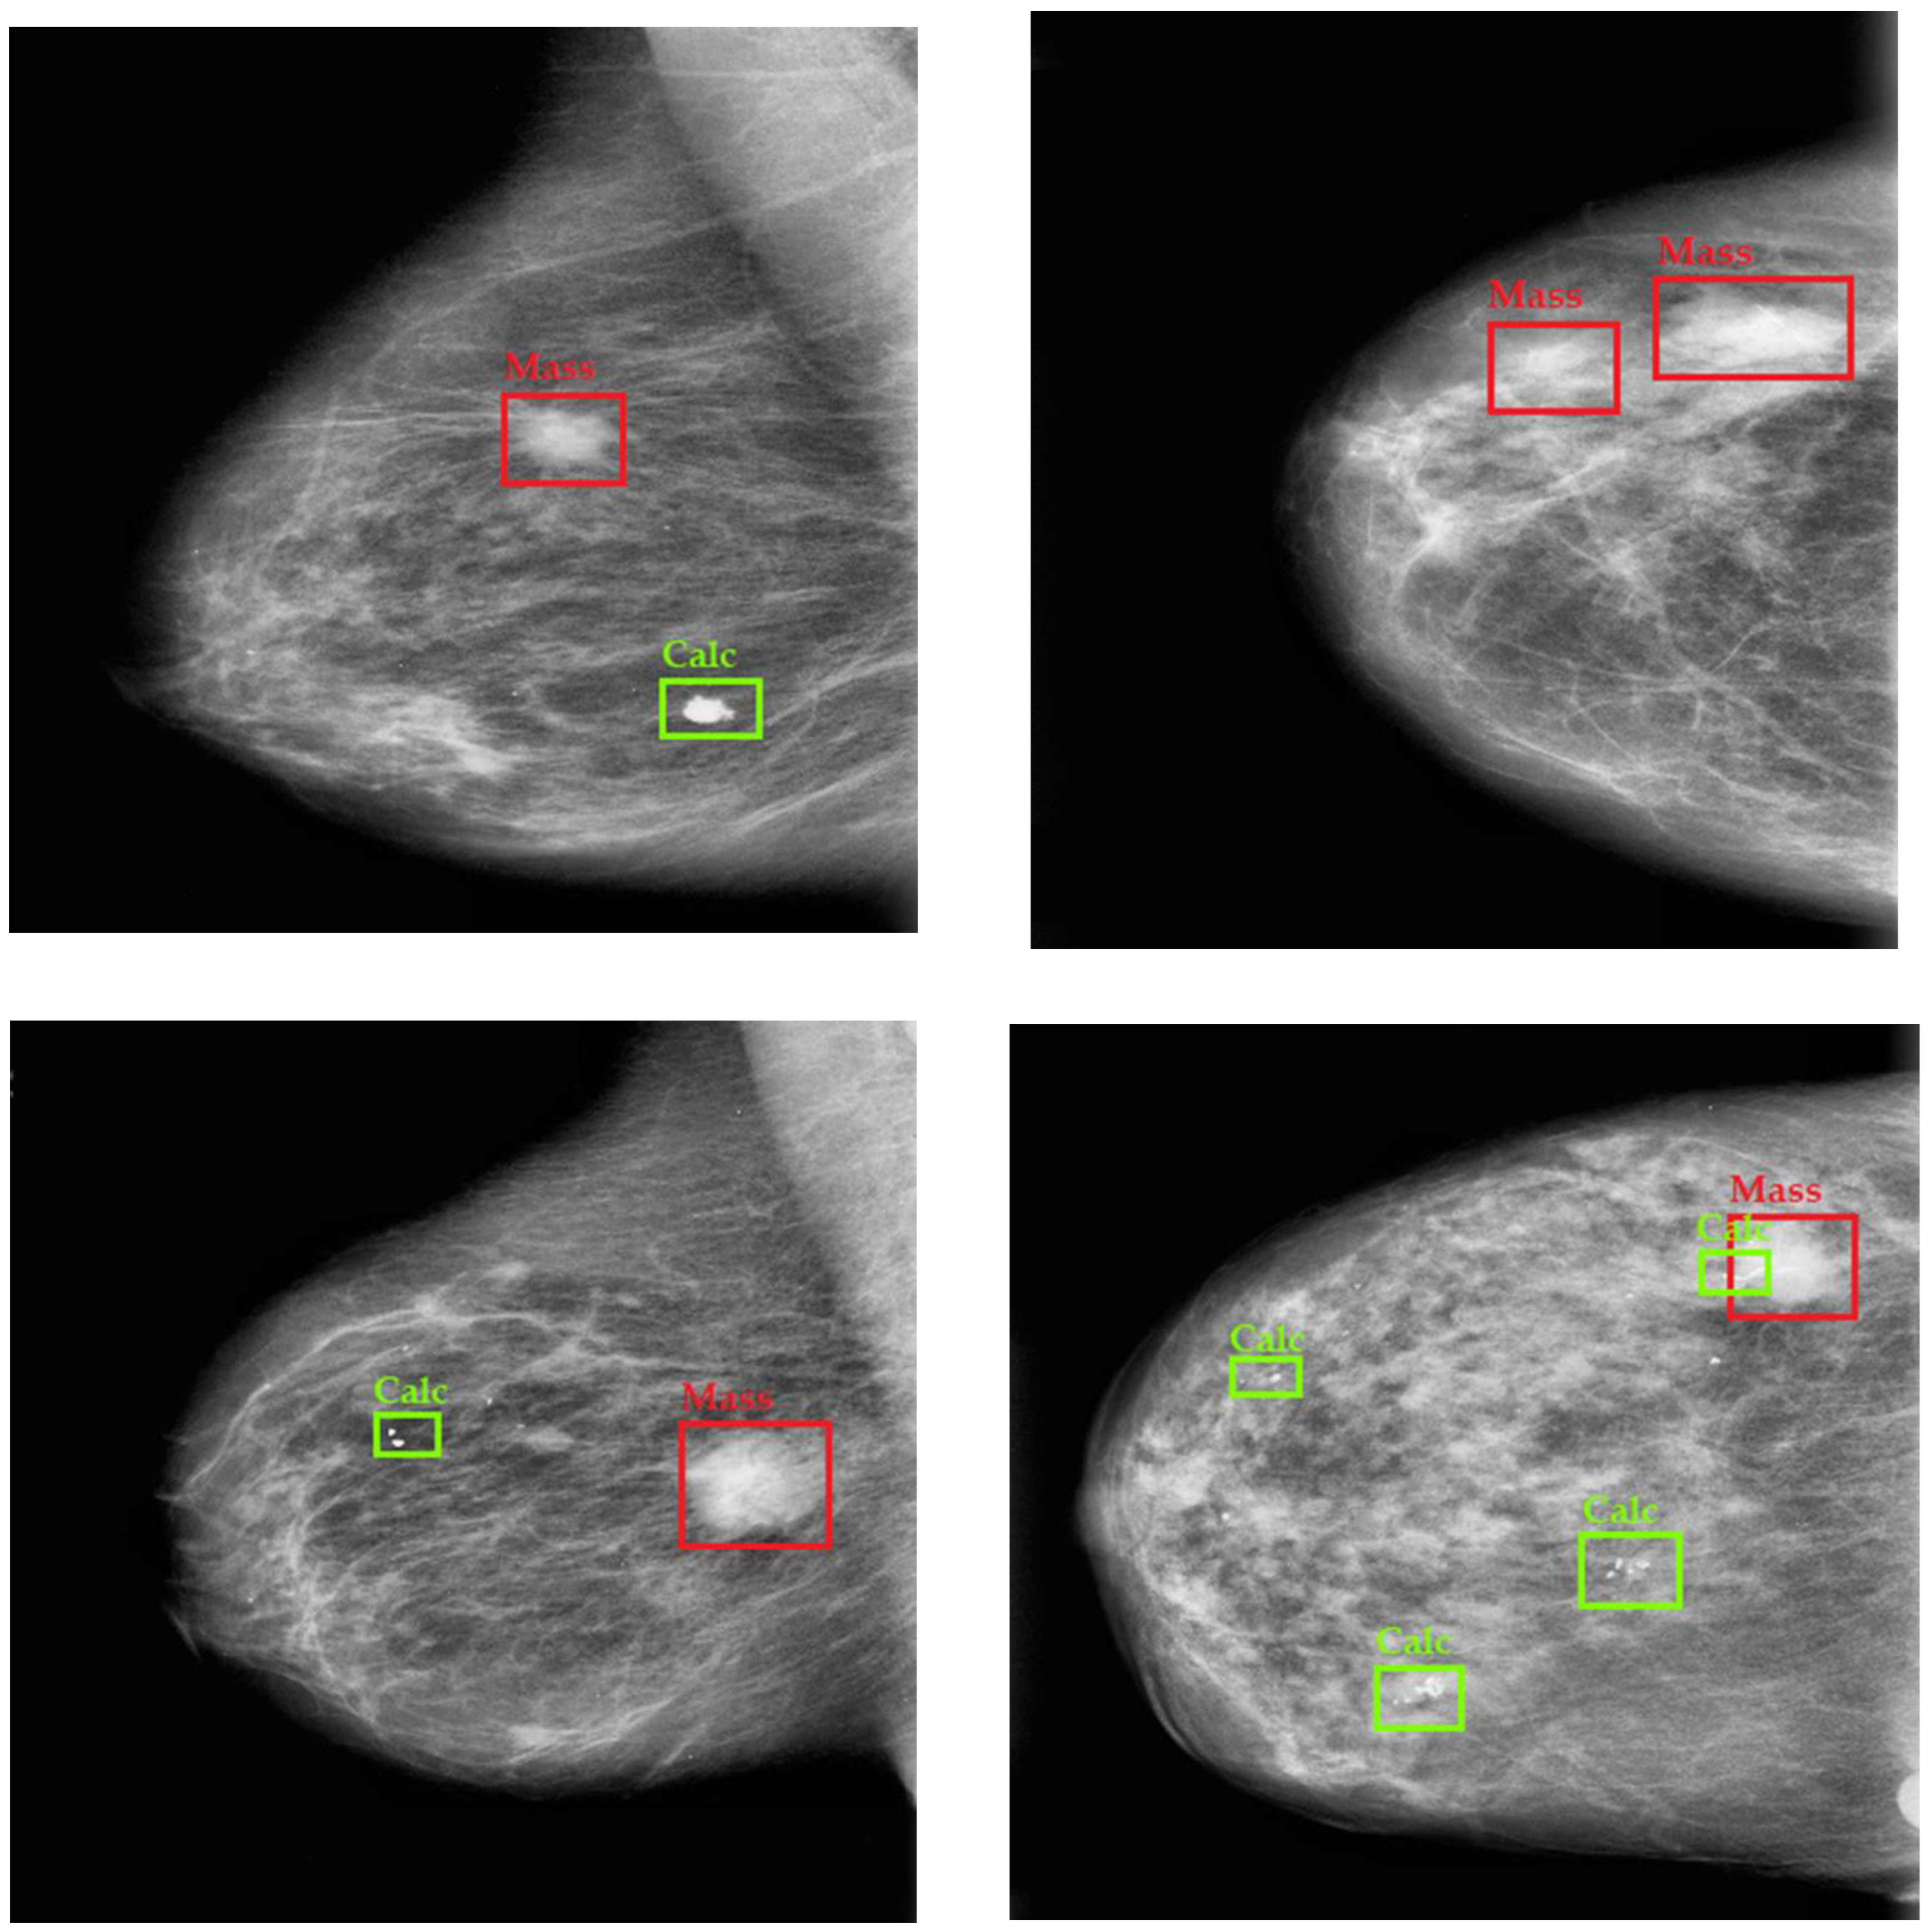

3. Results and Discussion

3.2. Ablation Experiment Breast Cancer Detection

3.3. Breast Cancer Detection Comparative Analysis